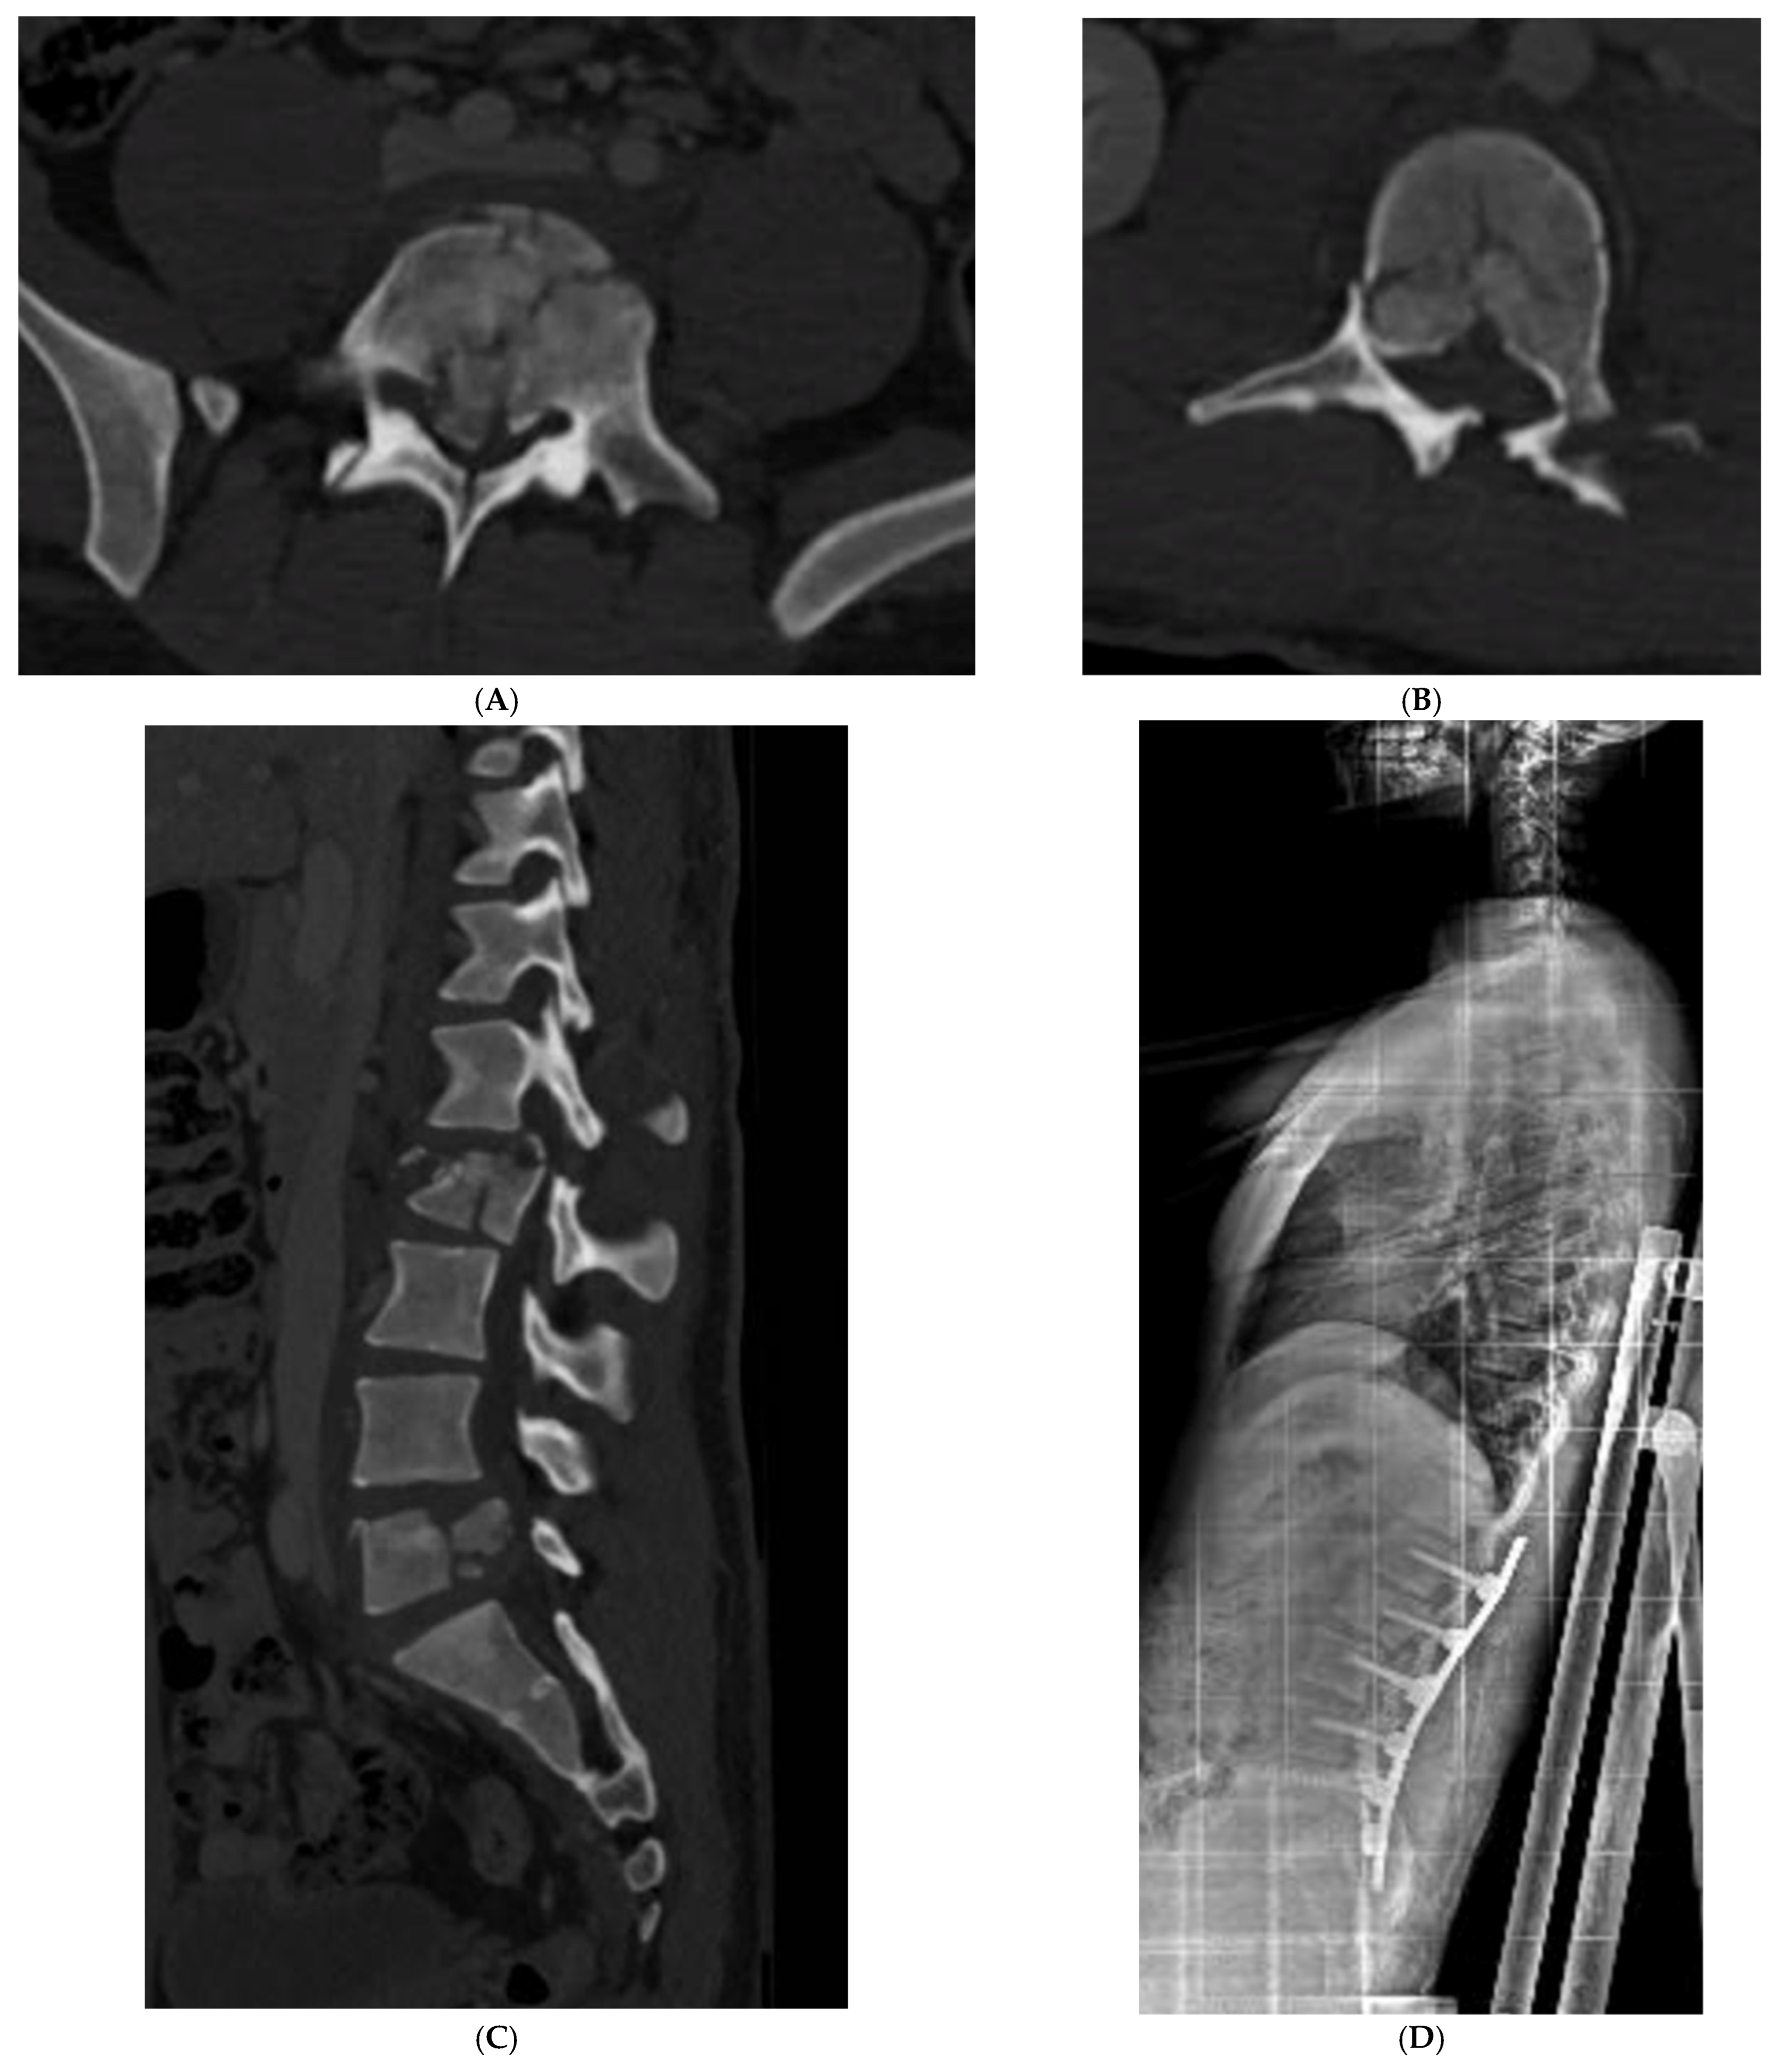

| Patient | Age | Sex | Vertebral Fracture—AO Classification | Other Fractures | Other Injuries | Spine Treatment | Hospitalization Days | Follow-Up | |

|---|---|---|---|---|---|---|---|---|---|

| 1 | V.C.G.C. | 15 y 9 m | F | L1 (A4), L4 (A1), Coccyx (A0) | right distal tibia, right fibula, left proximal humerus, left ulnar styloid process | pneumothorax, splenic injury, subdural hematoma, diffuse axonal injury | T12 to L2 Percutaneous pedicle fixation | 118 | 22 months No deficit Implant removal |

| 2 | A.M. | 14 y 1 m | M | L1 (A3) | right ankle | T12 to L2 Percutaneous pedicle fixation | 20 | 21 months No deficit Implant removal | |

| 3 | Z.P.E. | 14 y 11 m | M | L3 (A1), L4(A4) | right acetabulum, right ischiopubic branch, right tibia, bilateral wrist, bilateral heels | pneumothorax, aortic isthmus lesion, right peroneal nerve injury | L3 to L5 Percutaneous pedicle fixation | 37 | 17 months No deficit Implant removal |

| 4 | B.T.M.A | 12 y 7 m | F | D11 (A1) | multiple ribs | Conservative | 15 | 17 months No deficit | |

| 5 | R.S.M. | 16 y 1 m | F | D8 (A0), D11 (A1), L1 (A1), L4 (A1) | right ankle, left distal radius | Conservative | 12 | 11 months No deficit | |

| 6 | L.G.G. | 10 y 5 m | F | C2 (AD 2), C5 (A4), C6 (A1), L1 (A1), L2 (A3), L3 (A0), L4 (A0), Right sacroiliac joint | multiple ribs, right acetabulum, ilio-ischiopubic bilateral branch, left heel | liver injury, splenic injury, pleural effusion | Halo-Vest and L1 to L3 Percutaneous pedicle fixation | 64 | 10 months No deficit |

| 7 | H.B. | 15 y 5 m | F | L5 (A0), Sacral U-Shaped Fracture (C3) | right acetabulum, bilateral olecranos, right femural shaft | paraplegia, complete neurogenic bowel and bladder dysfunction | L4 to Pelvis posterior open fusion, left sacral plate and L4 to S1 decompression | 30 | 8 months complete neurogenic bowel and bladder dysfunction; motor deficit of the right limb partial recovered |

| 8 | D.G. | 12 y 10 m | F | D6 (A1), D7 (A1) | multiple right ribs | pneumothorax | D5 to D8 Percutaneous pedicle fixation | 210 | 9 months No deficit Implant removal |

| 9 | M.D. | 16 y 5 m | M | D12 (A1), L1 (A3) | anal injury | T10 to L2 Percutaneous pedicle fixation | 56 | 6 months No deficit | |

| 10 | G.A. | 16 y 6 m | M | L2 (A4), L5 (A4) | right orbital maxilla surface, right open tibia and fibula | L1 to S1 Percutaneous pedicle fixation | 40 | 6 months No deficit | |

| 11 | B.V. | 15 y 3 m | F | L1 (A4) | pulmonary contusion, complete neurogenic bowel and bladder dysfunction | T11 to L3 open pedicle screw fixation and posterior L1 decompression | 14 | 1 month Urinary retension | |

| 12 | P.E. | 12 y | F | L5 (A0), Sacral fracture (B3) | orbital floor, bilateral nose bones, ilio-ischiopubic left branch, pubic symphysis diastasis | L4 to ilium left open fixation and iliosacral screw | 33 | 1 month No deficit |